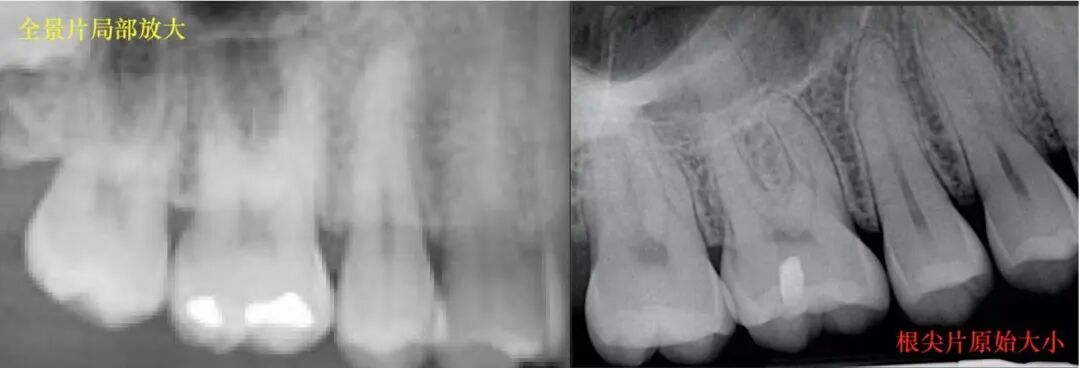

四. 如何判断自己有没有牙周病?

五. 诊断牙周炎需要做哪些检查?